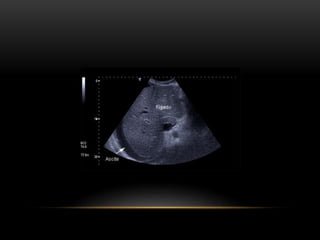

ASCITE

• Acúmulo anormal de líquido seroso na cavidade peritoneal

• Associada principalmente a causa hepática

• Classificada como transudato ou exsudato, ou com ou

sem hipertensão portal.

• Lembrar calcular o Gasa, se maior que 1,1, 97%

hipertensão portal.

• Paracentese diagnóstica/de alívio caso medicamentos

diuréticos não atinjam objetivos